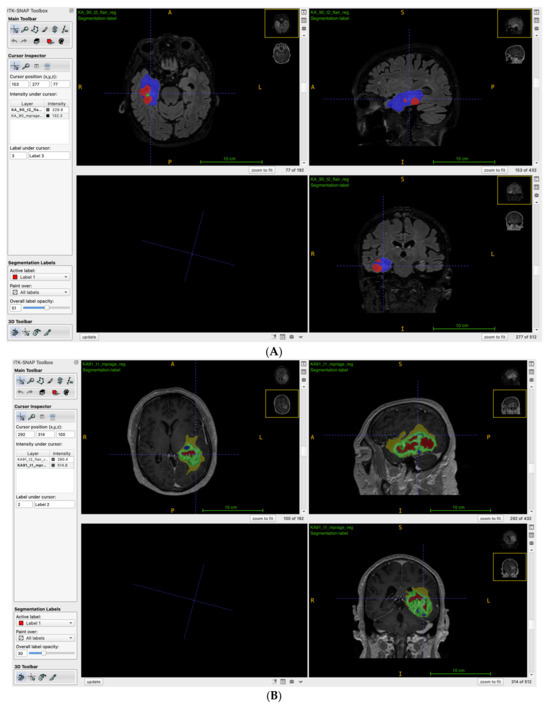

4.5. Segmentation

| Jiang et al. [29] | Manual segmentation + ITK-SNAP (http://www.itksnap.org/pmwiki/pmwiki.php) accessed on 15 November 2024 | Not specified | FSL | Pyradiomics (https://pyradiomics.readthedocs.io/en/latest/) accessed on 15 November 2024 |

| He et al. [44] | Manual Segmentation | Not specified | ITK-SNAP | Z-score |

| Doniselli et al. [47] | Semi-automatic—ITK-SNAP | SPM12 (https://www.fil.ion.ucl.ac.uk/spm/software/spm12/) accessed on 15 November 2024 | ANTs | Z-score |

| Sha et al. [26] | Manual segmentation + ITK-SNAP | Not mentioned | FSL | Intensity Normalization + Z-Score |

| Li et al. [25] | 3D U Net + ITK-SNAP | Not specified | MatLab | Z-score |

| Zheng et al. [55] | Manual segmentation + ITK-SNAP | Not mentioned | FSL | PyRadiomics |